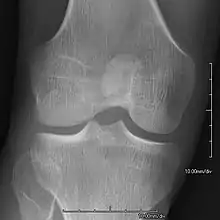

Bones and joints

- Patellar involvement is present in approximately 90% of patients; however, patellar aplasia occurs in only 20%.

- In instances in which the patellae are smaller or luxated, the knees may be unstable.

An elbow of a man with nail–patella syndrome (NPS)